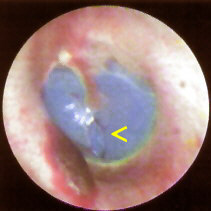

Figure 1. Video otoscopic image of "tympanic cavity impression"

taken in ENT office. Click image for full size view.

The vivid blue cast visible through the tympanic membrane in Figure 1 is the residual silicone impression material filling the middle ear space in intimate contact with the medial surface of the TM. Injection of the material caused a traumatic inferior perforation of the tympanic membrane and subsequently filled the tympanic cavity. Note the hematoma in anterior inferior auditory meatus, probably traumatically induced by the injection gun tip placement.